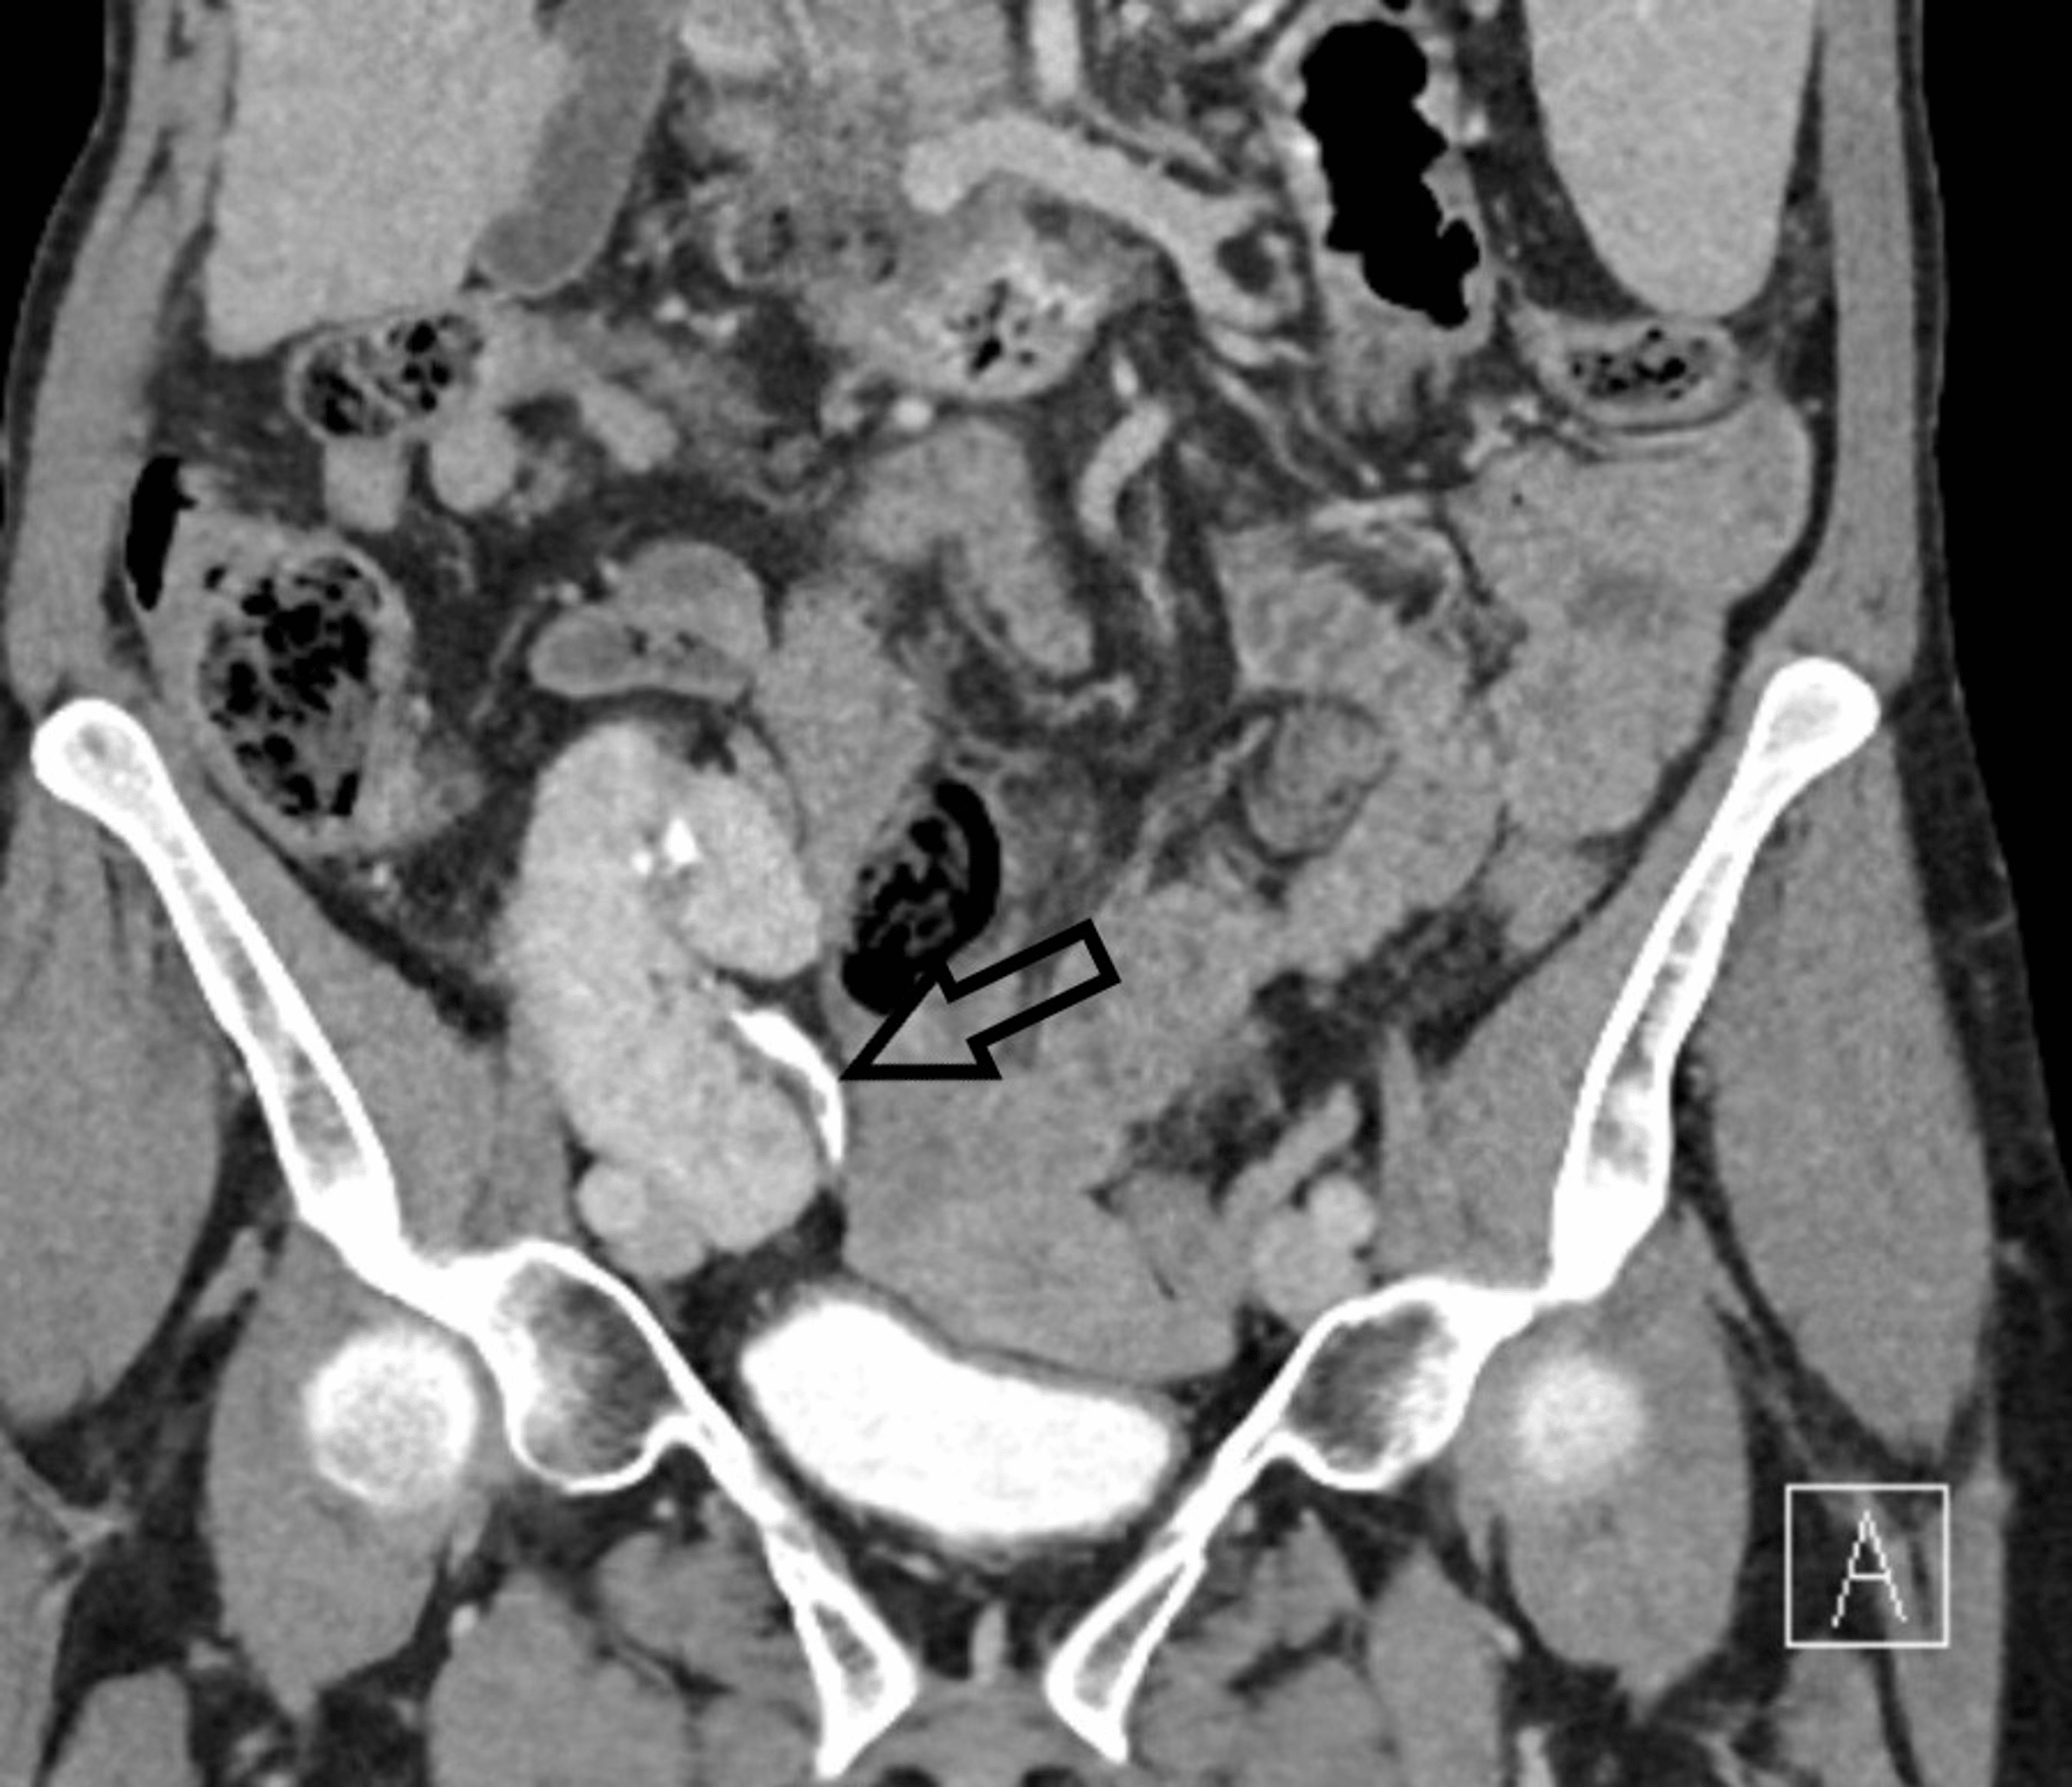

Radiology (a) CT scan coronal view showing the gallbladder filled with Radiolucent Stones Ct Web urinary matrix stones are a rare form of urinary calculi that are typically radiolucent. Web unenhanced computed tomography (ct), first introduced for stone imaging in the 1990s, has since emerged as the reference gold. Web if an unenhanced ct is insufficient to delineate the difference between a phlebolith or a urinary calculus, a delayed. Web the application of noncontrast. Radiolucent Stones Ct.

From www.eurorad.org